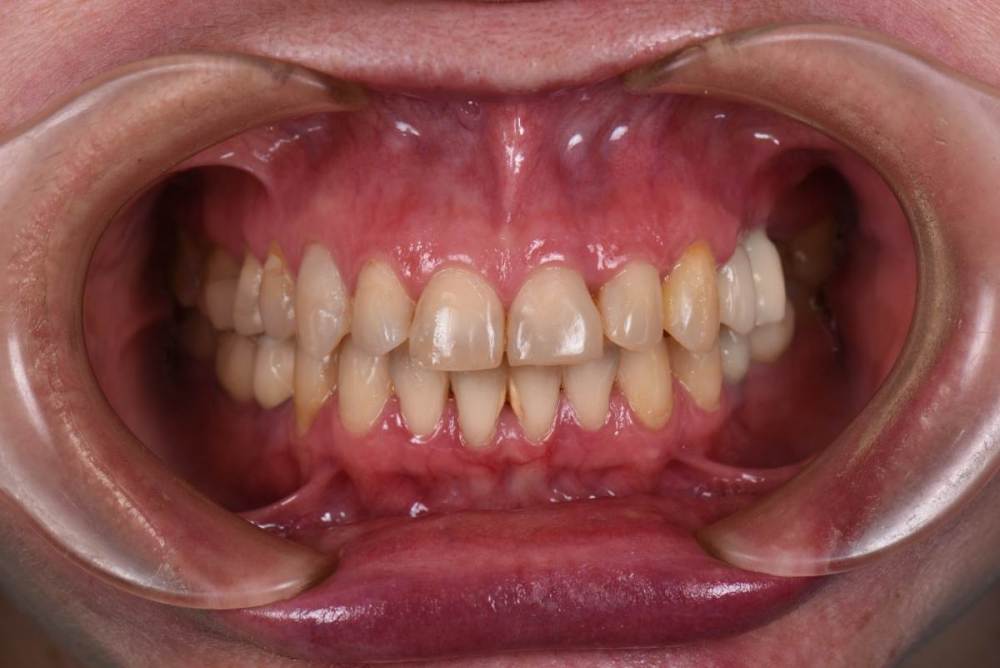

До:

Закончил тотал и решил поделиться. Протезировали с учетом положения ВНЧС в концепции Славичека.  В конце изготовление брукс чекеров для проверки нежелательных контактов во время сна.  Гигиену пытаемся победить...